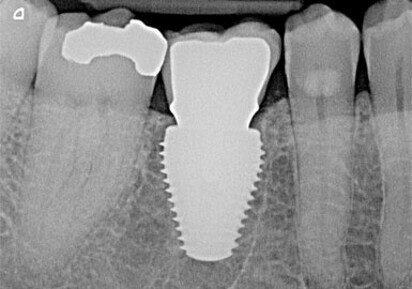

A multi-rooted extraction socket is often too large to accommodate a regular size implant. Often use of standard dental implants requires bone grafting and delayed implant placement, lengthening the patients’ treatment time and adding costs. Additionally, single root placement might require surgical and prosthetic compromises. Keystone Dental has designed dental implant lines for specific indications.

The MAX ultra wide platform implants allow for improved molar emergence profiles to reduce the size of gingival embrasure spaces and, therefore, reduce the potential for food impaction.